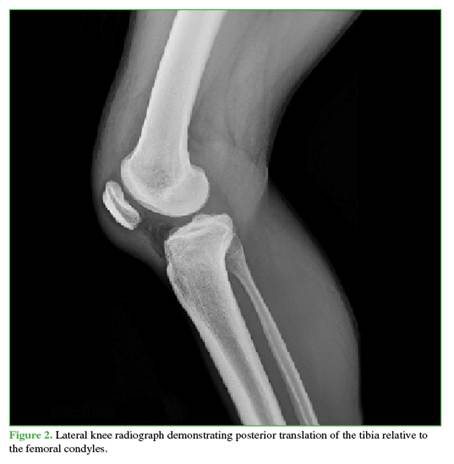

A 27-year-old male farmer residing in a rural area, with no relevant medical history, suffered a traffic accident after falling into a ravine while riding a motorcycle, resulting in trauma to his right shoulder and knee. He initially sought care at a rural hospital, where marked edema, ecchymosis, and a positive dimple sign were identified in the right knee. He also had limited range of motion in both the shoulder and the knee. As X-rays were not available, he was referred to a hospital with orthopedic services. There, initial radiographs were obtained (Figures 1 and 2), documenting a diaphyseal humeral fracture that was immobilized with a sugartong splint. In addition, a posterolateral knee dislocation and a lateral patellar dislocation were diagnosed. Two orthopedic surgeons attempted three reductions under sedation (no anesthesia was available), successfully reducing the patella but not the knee. It was decided that the patient required transfer to a trauma center for urgent open reduction and to rule out an associated vascular injury. The knee was immobilized with a bivalved hip-to-foot splint and he was referred.